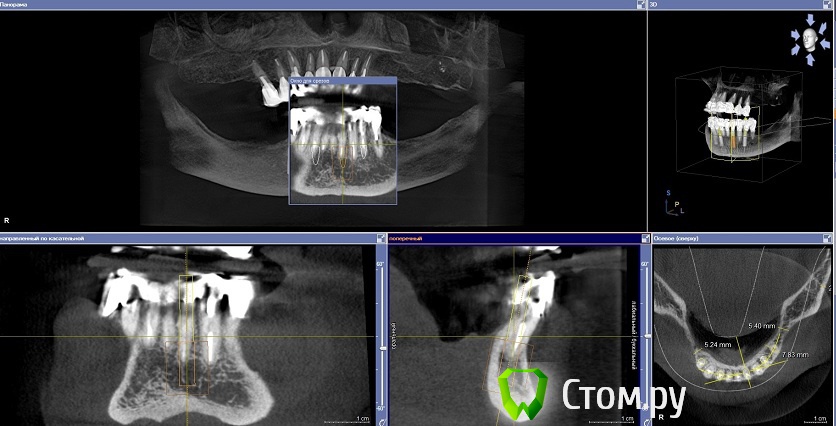

Dr.Sham Опубликовано 14 октября, 2014 Поделиться Опубликовано 14 октября, 2014 (изменено) Планируется удаление всех зубов на НЧ. Пациентка хочет несъемную конструкцию.Вот нарезка.Планируется имплантация Ankylos в позициях 46, 44, 42, 32, 34, 36.В боковых отделах дефицит всего.Думаю удалить зубы через один, чтобы на них временная конструкция держалась, а в промежутках имплантаты.В переднем отделе узко, либо узкие ФДМки, либо заглушка и в овоид край времянок или закрыть свободным трансплантатом.Что думаете?В боковых отделах вопрос...короткие имплантаты и НКР? От сложной костной пластики пациентка отказывается категирочески. Сверху пациентка так же хочет несъем. Поэтому все на 4-х, наверное, не самамя удачная конструкция здесь. Зубы сохранить никак, преп под десной местами по 3 мм. ну и дентин весь мягкий. Изменено 14 октября, 2014 пользователем Dr.Sham Ссылка на комментарий

MayTaraki Опубликовано 14 октября, 2014 Поделиться Опубликовано 14 октября, 2014 Всё на 6 В боковых отделах НКР там 1- 2 мм не хватает по сути Ссылка на комментарий

Mane Опубликовано 15 октября, 2014 Поделиться Опубликовано 15 октября, 2014 Добрый вечер. Можно вариант Дмитрия. А можно и : Ваксап 12 зубов на н/чОртопедический шаблон на н/ч Операция: удаляете все сразу 4 имплантата 34-32-42-44 - по длиннее - чтоб торк точно был. В боковых отделах поставьте коротыши и НКР по толщине сделайте. перед установкой имплантатов, как сказал Дмитрий, выровняйте гребень во фронтальном отделе - чтоб с боковыми отделами не было большого перепада - коромысла. Срузу после операции нагружайте эти 4 имплантата несъемной конструкцией лабораторного изготовления. Если требуется, можно и по десне поработать в первую операцию. Удачи. На анкилозе есть же коротыши! 4 Ссылка на комментарий